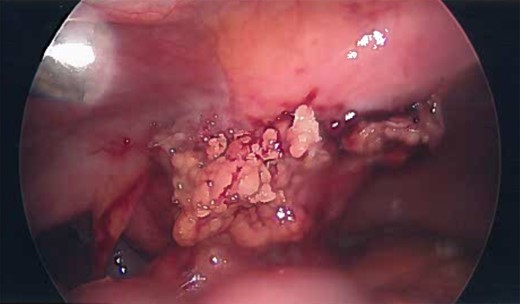

Inflamed and necrotic appearance of the urachal cyst with multiple pus filled cavities.

Gross appearance of the urachal cyst resembled an inflammatory and necrotic appearance with multiple cystic cavities (Figs 3 and 7). On pathology, tentative diagnosis of the specimen was confirmed as an urachal cyst. The appearance of an ulcerated cyst wall noted with marked fibrosis, acute and chronic inflammation with focal abscess, foreign body giant cells, and fibrous adhesions, consistent with history of infected urachal cyst and no evidence of malignancy. Intra-operative culture of urachal cyst provided contents positive for Escherichia coli, and negative for fungal material. The patient had an uneventful post-operative course. We followed up the patient in 2 weeks and again in 3 months in the outpatient clinic. During the follow-up, patient reported that removal of the cyst helped her abdominal pain, urinary tract symptoms have completely resolved and constipation was improve pertinently.